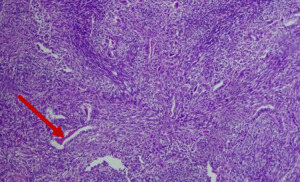

Grossly, the tumor measured 7x6x3cm, appeared solid and encapsulated (Figure 3a). Histologic examination (by hematoxylin and eosin staining) showed a high-grade sarcoma consistent with biphasic synovial sarcoma. Microscopic evaluation showed solid proliferation of plump spindle cells with hyperchromatic nuclei and variable sized nests of glands lined by columnar cells, some glands containing eosinophilic secretions with areas of necrosis and calcification (Figures 3b and 3c). Genomic testing was not available in our hospital (or elsewhere in Ethiopia) for further confirmation of the histologic diagnosis or the fusion subtype.